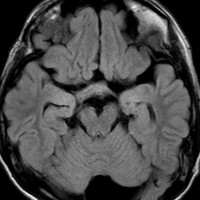

化学療法が有効なのは,上の画像のようにガドリニウム増強で強く増強されるタイプです,またT2強調画像で強い高信号になるものほど化学療法が有効です,要するに毛様粘液性星細胞腫の要素に化学療法が有効であるということです

この毛様細胞性星細胞腫はガドリニウムでほとんど増強されません(右側のMRI)から,化学療法を行っても小さくなりませんので,手術摘出する必要があります,実際に視床下部から発生したもの視交叉が犯されておらず,手術亜全摘出できました